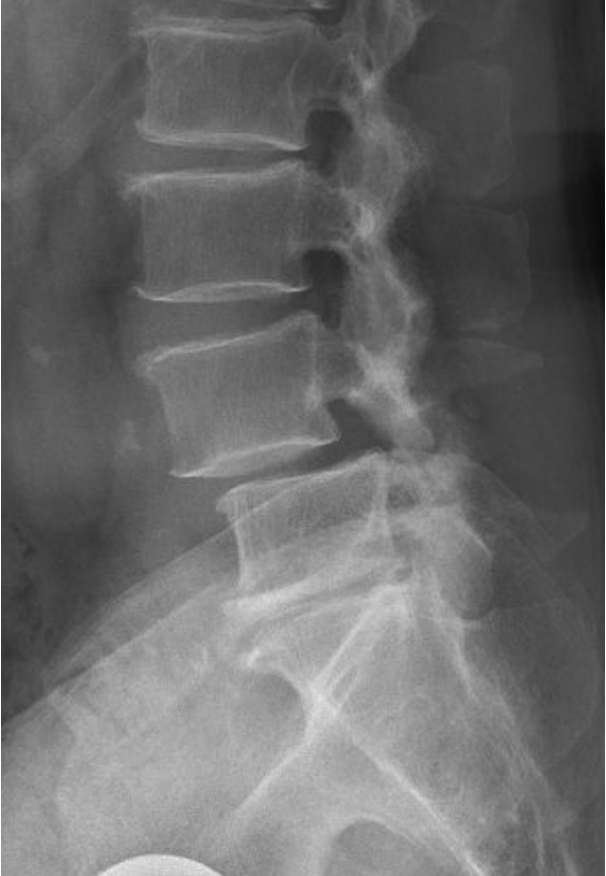

X-ray image of a human lumbar spine showing vertebrae and discs.

• X‑rays clearly show how much one vertebra has shifted relative to another.

• MRI shows nerves, discs, and areas of stenosis.

• Symptoms and nerve compression are often more important than the exact amount of slip.